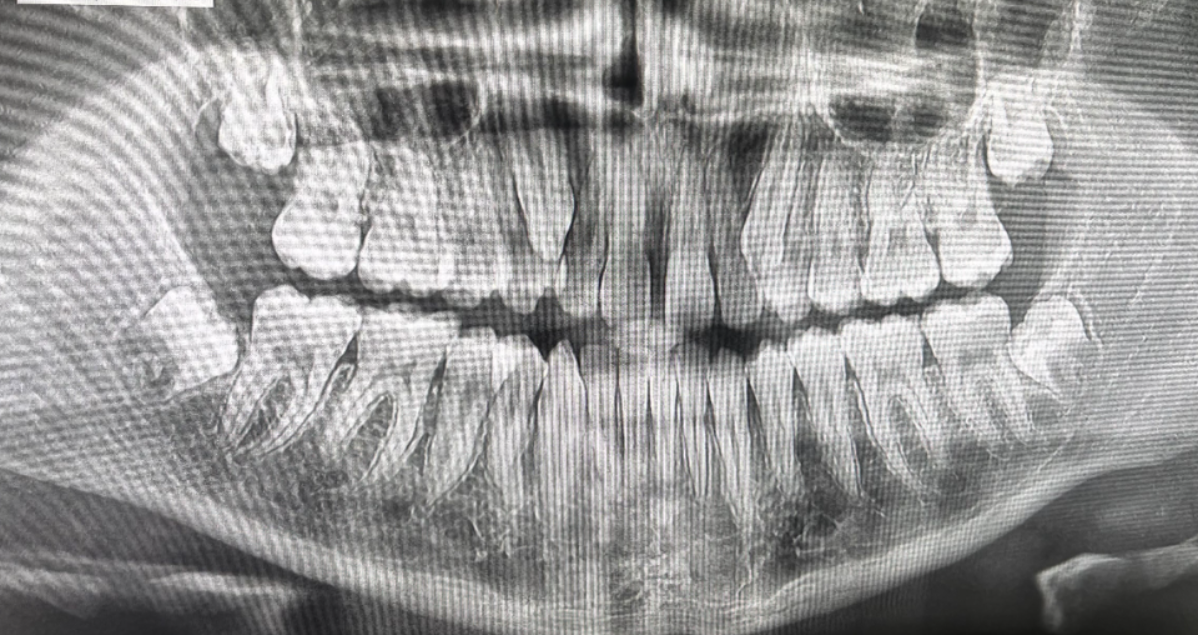

En este trabajo vamos analizar los principales problemas que se pueden ver en la radiografía, como las raíces, el hueso maxilar y mandibular, así como la posicion de las muelas del jucio y la posición incorrectas de los incisivos, caninos, premolares y molares.

Podemos observar las cuatro muelas del juicio (terceros molares)

Ambas muelas del juicio inferiores están incluidas y en posición horizontal, empujando contra los segundos molares

Esto puede provocar: dolor , infecciones y Daño en las raíces del segundo molar.

También presentan mala posición y falta de espacio.

podemos hacer el tratamiento de extracción quirúrgica de las muelas del juicio.